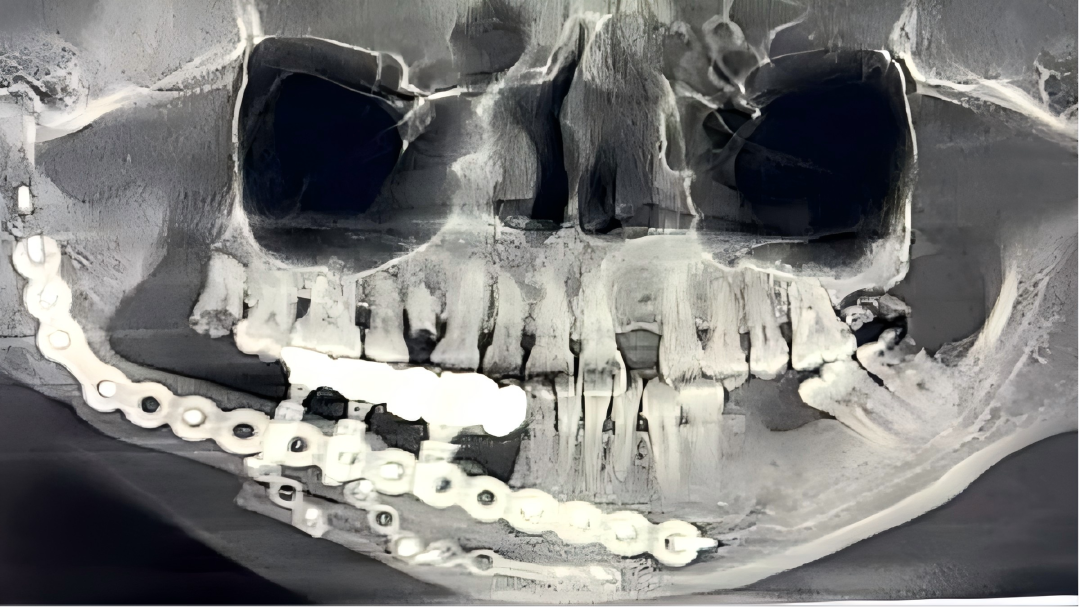

3.颌骨缺损精准重建

针对肿瘤、放疗或药物等因素导致的颌骨病变,以及在大范围切除术后造成的骨缺损问题,科室开展数字化(计算机辅助设计、3D打印)引导下的游离腓骨肌皮瓣移植术,实现颌骨的精准重建;并创新开展“移植腓骨同期种植”技术,在恢复面容外貌美观的同时,更有效重建咀嚼功能,全面提升患者生活质量。此项综合重建技术难度高,目前在省内能常规开展的医院屈指可数,整体水平达到国内前沿、省内先进。

科室自2007年起开展血管化游离骨瓣重建颌骨缺损手术,历经十余年技术迭代,实现了从单段到多段截骨、从单侧重建到双侧重建、从模型辅助到数字化设计与3D打印,从单纯骨组织修复到移植骨同期种植恢复咀嚼功能。每一步都紧跟前沿,每一次升级都只为更精准的治疗,使众多患者术后得以重返社会、重返生活。